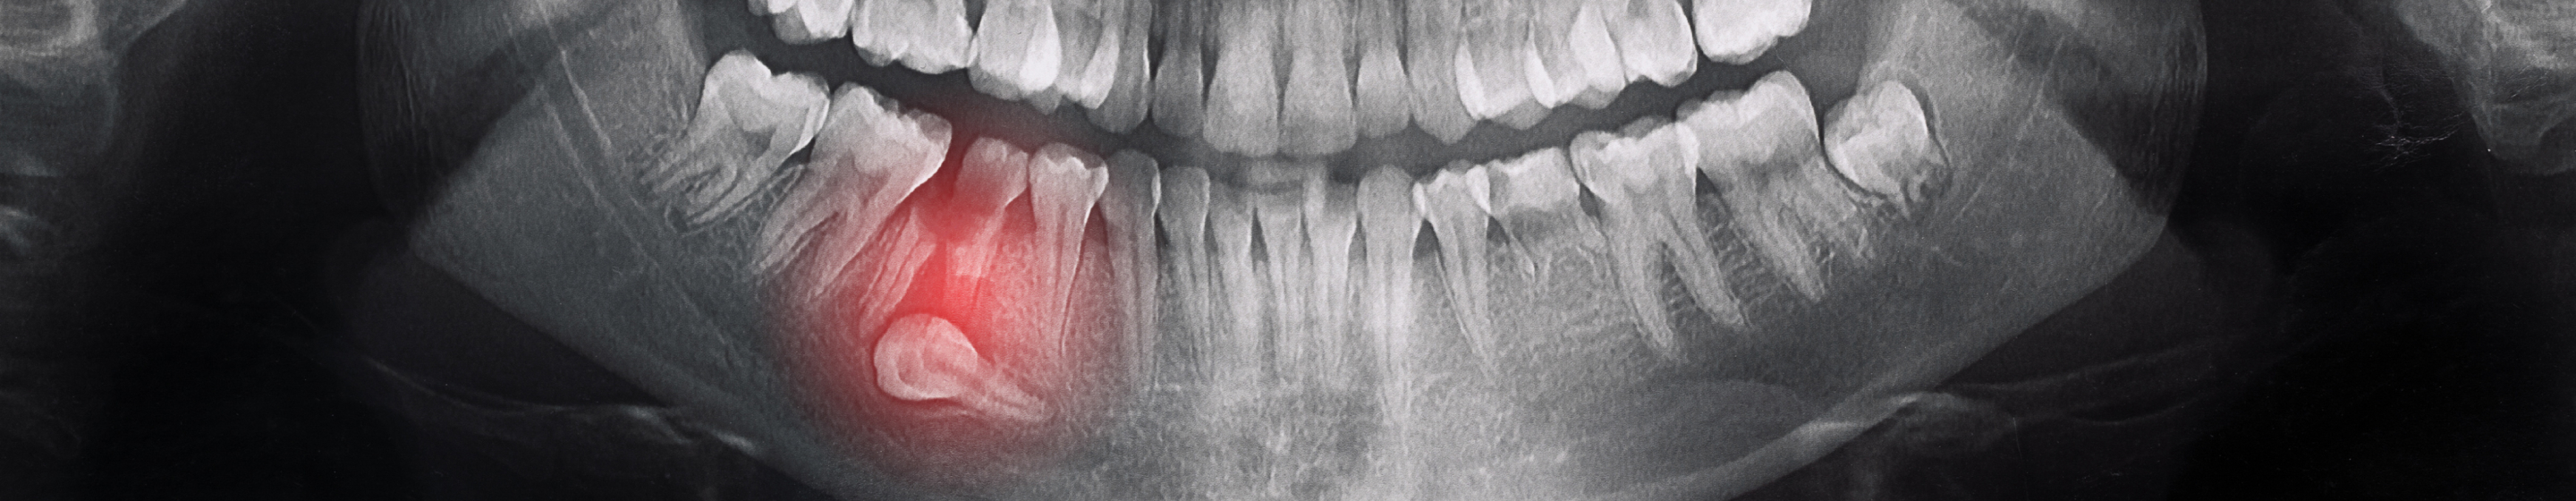

③ 嚢胞(骨の中の病変)ができることも

レントゲン・CT検査で初めて見つかることも多く、放置すると顎の骨を圧迫して変形させたり、周囲の歯を巻き込む危険性があります。

CT解析による立体診断 ― リスクの「見える化」

親知らずの判断に欠かせないのが 歯科用CTによる三次元解析 です。

レントゲンでは平面でしか状況を把握できませんが、CTは以下を立体的に確認できます。

• 神経(下歯槽神経)との距離

• 骨の厚み・形態

• 歯根の湾曲や分岐の状態

• 親知らずがどの方向に向かっているのか

• 嚢胞(骨の病変)の有無

これらの情報を正確に把握することで、術中の不要な出血や神経トラブルを避ける戦略を立てることが可能になります。